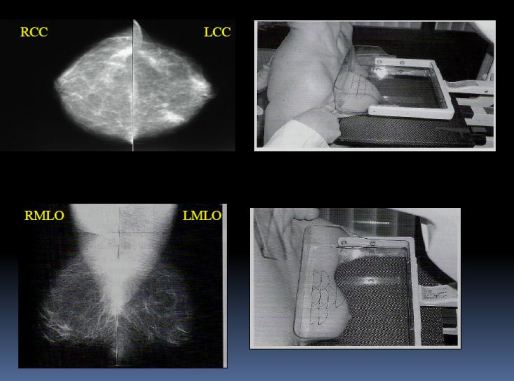

Mamografické vyšetření

- Je prováděno na speciálních mamodiagnostických odděleních, speciálně školenými laborantkami

- Je trochu nepříjemné, žena při vyšetření stojí

- Každý prs je vyšetřen ze dvou stran, pokaždé se musí lehce stlačit

- Vniklé mamografické snímky hodnotí lékaři

- NUTNOST kvalitně zhotovených snímků!!!

- Mamografie je standardní vyšetřovací modalita

- Pro diagnostiku jsou technicky správně zhotovené snímky základem